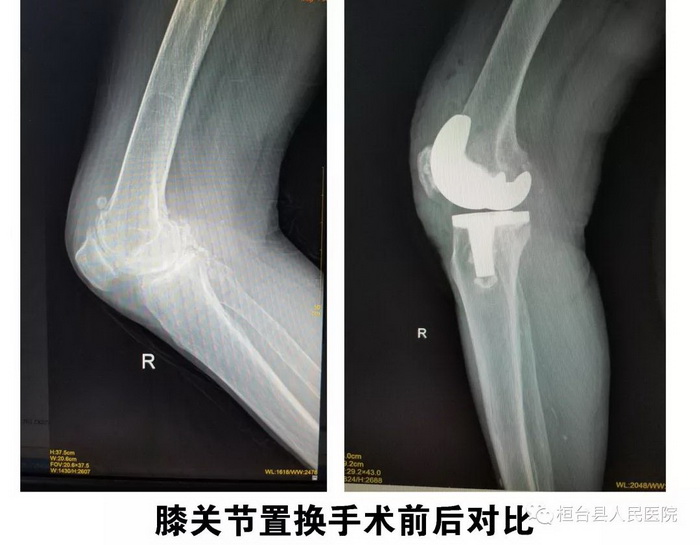

科室简介

骨科一病区现有医护人员22名,其中副主任医师3名,主治医师6名,硕士研究生3名。开放床位50张。医院拥有国内先进的现代化层流净化手术间、双源CT、1.5T磁共振、术中C臂、G臂透视机、关节镜、脉冲冲洗器等高标准手术间及先进的检查、手术设备。 科室先后派遣人员到北京大学第三医院、积水潭医院、解放军第301医院、北京协和医院、山东大学齐鲁医院、山东省立医院、海军401医院等多家医院进修学习。每年完成手术近千例,包括人工膝关节表面置换术、全髋关节置换术、翻修术,关节镜下前、后交叉韧重建术、髌股内侧韧带重建术以及脊柱疾病手术等高难度手术。其中人工膝关节置换手术是医院在全县率先独立开展的高难度手术,均取得良好手术效果,术后患者满意高。 骨科一病区在医院党委领导下始终坚持“以病人为中心,以质量为核心”的服务宗旨,不断提高技术水平,为全县及周边膝关节疼痛患者提供更加优质、安全的医疗服务。